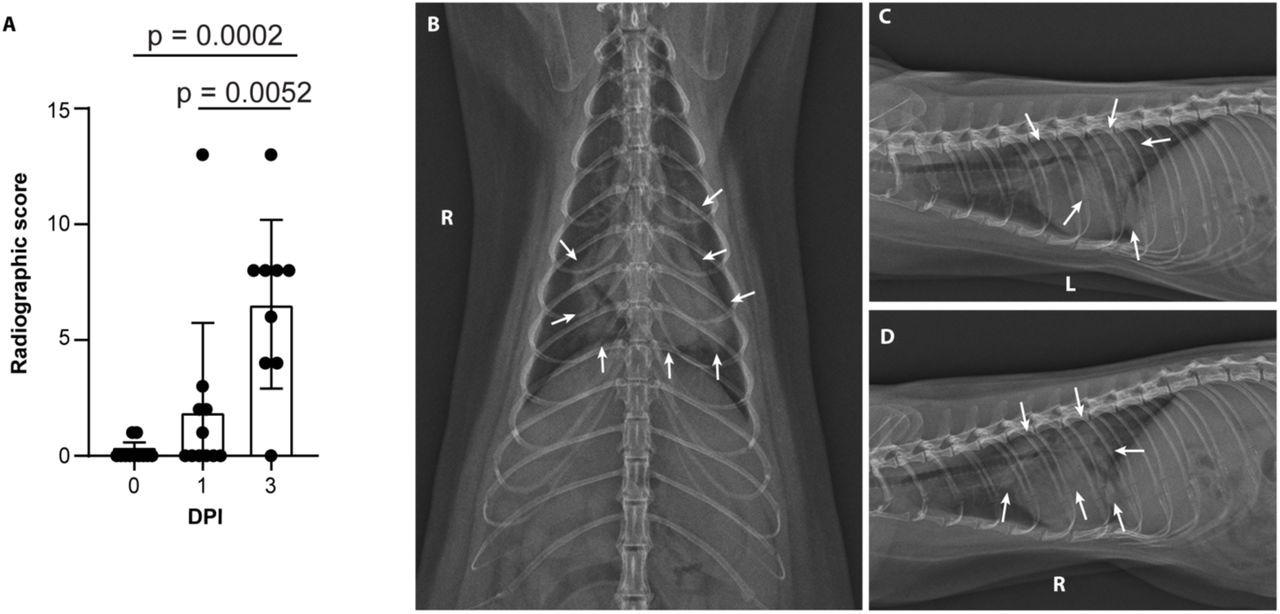

Severe radiological changes after infection with SARS-CoV-2. (A) Compiled radiographic scores. Bar graph depicts the mean with standard deviation and individuals, ordinary one-way ANOVA with Tukey’s multiple comparisons test. Radiographs demonstrate multifocal pulmonary infiltrates, most severe in the left and right caudal lung lobes depicted in the (B) dorsoventral radiograph (C) left lateral and (D) right lateral radiograph on the evening of 2 days post-inoculation (DPI). Arrows depict grade 4 pulmonary disease in the left and right caudal lung lobes with grade 3 pulmonary disease in the right middle lung lobe and cranial subsegment of the left cranial lung lobe.

Minks developed progressive pulmonary infiltrates consistent with viral pneumonia from ARDS on the first and third day after exposure.